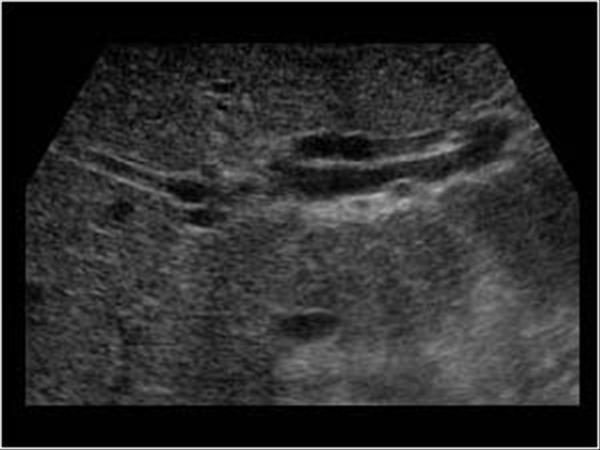

Main lobar fissure

A groove that divides the Rt lobe of the liver into anterior and posterior segment

Rt intersegmental fissure

Which anatomical structure is located within the Rt Intersegmental fissure?

Right hepatic vein